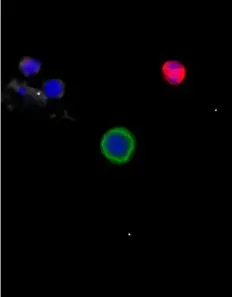

Example images from patient blood samples

Cluster of epithelial CTCs - breast

Examples of Portrait+ CTC staining kit samples